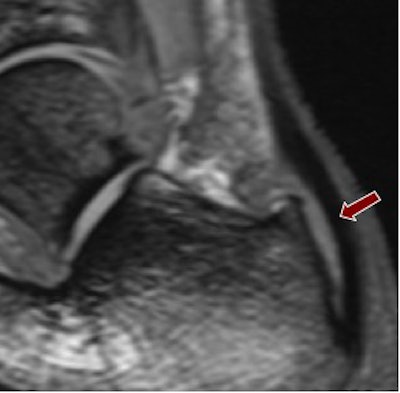

Fluid collection around tendons was apparent in all six runners at both field strengths, though visibility of this was clearer at 7-tesla using a multiple-echo data image combination (MEDIC) sequence, which produced a high contrast with the surrounding tissue.

| Above, 1.5-tesla image of bursal fluid in the ankle. Below, 7-tesla image shows superior depiction of the bursal fluid. Images courtesy of Dr. Patrick Kokulinsky. |